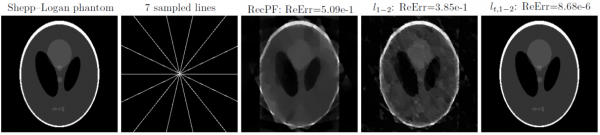

图:马天咴的实验结果表明,他提出的方法(右一)仅通过7条采样线成功重建了256×256 Shepp-Logan phantom图像,这是已知方法所需采样线数目的最低值。

在这次修改中,他尝试用自己的方法,重建了Shepp-Logan phantom图像。这是医学图像处理领域用来进行仿真测试的标准模拟图像,由一些大大小小的椭圆来模拟生物器官。12年前,“压缩感知”的发现者伊曼纽尔·坎迪斯正是用这张图片测试了名为“L1-范数极小化”算法。

一般来说,重建同样规模的数据所用的观测数据越少,就越能说明重建的效率更高。马天咴测试的结果是:他只需要用7条采样线就能成功重建256×256 Shepp-Logan phantom图像。这是已知方法所需采样线数目的最低值,比陶哲轩、坎迪斯、隆伯格等先行者的方法更好。